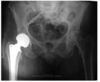

Identify the Image

Hip Replacement